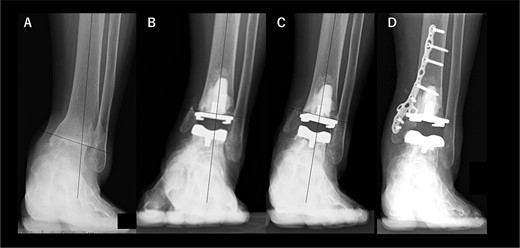

A 72-year-old man with end-stage ankle OA and severe ankle joint pain and gait dysfunction had a JSSF ankle/hindfoot scale score of 42 points. Talar tilt was 11° varus (Fig. 1A). He underwent TAA with medial malleolar osteotomy without internal fixation, and the tibial component was placed in the 5° varus position (Fig. 1B). Within 6 months, the tibial component showed varus migration, and nonunion at the medial malleolar osteotomy occurred (Fig. 1C). Revision TAA with mini-plate fixation at the medial malleolus was then performed (Fig. 1D), but the tibial component was still placed in the varus position (3° varus); subsequently, varus migration of the tibial component occurred again (Fig. 1E). After that, vitamin D administration and low intensity pulsed ultrasound treatment were continued for more than 1 year, and bone union was achieved, but both the tibial and talar components showed malposition (Fig. 1F). At present, four years after revision TAA, he can walk for more than 1.5 hours and play golf.

Radiographs of preoperative weight-bearing radiograph of the antero-posterior ankle joint in Case 1. (A) Preoperative. Talar tilt is 11° varus. Opening of the lateral gutter with os subfibulare is seen. (B) One month after surgery. Medial malleolar osteotomy without internal fixation, and tibial component placed in the 5° varus position. Opening of the lateral gutter still remains. (C) Five months after surgery. The tibial component shows varus migration, and nonunion at the medial malleolar osteotomy has occurred. Opening of the lateral gutter is exacerbated. (D) One month after revision surgery. The site of the medial malleolar osteotomy is fixed with a mini-plate, and varus positioning of the tibial component still remains (3° varus). The lateral gutter is closed. (E) Three months after revision surgery. Varus migration of the tibial component has occurred again, and bone union at the osteotomy is still not seen. (F) Four years after revision surgery. Bone union has been achieved, but both tibial and talar components show malposition. The lateral gutter is still closed.